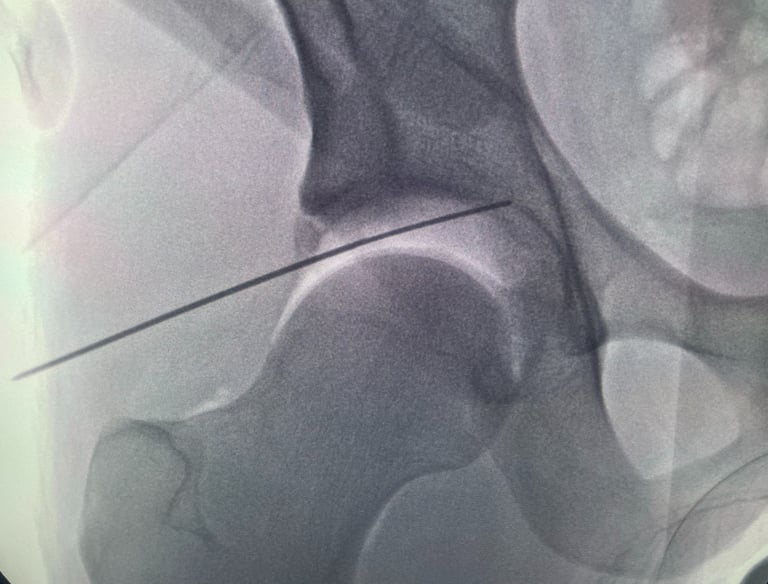

Cirugía Mínimamente Invasiva

Enfocada en recuperación rápida y menos dolor postoperatorio para los pacientes.

Galería Médica

Imágenes de procedimientos y técnicas en cirugía de cadera.